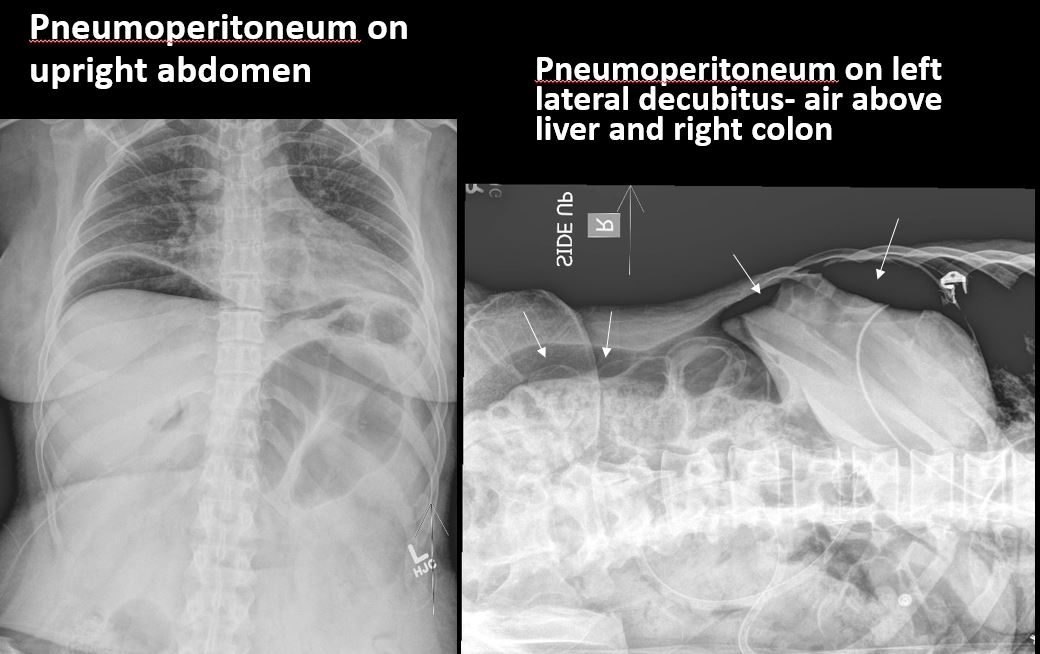

There is free air beneath the diaphragm. |

No | NA |

There is scattered extraluminal air or an abnormal focal collection of air in the abdomen or pelvis. |

Yes | NA |

There is air in the retroperitoneum. |

There is free air beneath the diaphragm or above the liver or right colon. |

N/A | NA |

There is extraluminal air in the soft tissues of the abdomen which could be from necrotizing fasciitis. A CT scan and urgent surgical consult are recommended. There is airspace disease or atelectasis in the left lung base.

Notify the clinical team verbally and immediately about possible necrotizing fasciitis and need for urgent surgical consult.

Emergent: non-routine communication required immediately or within 30 minutes